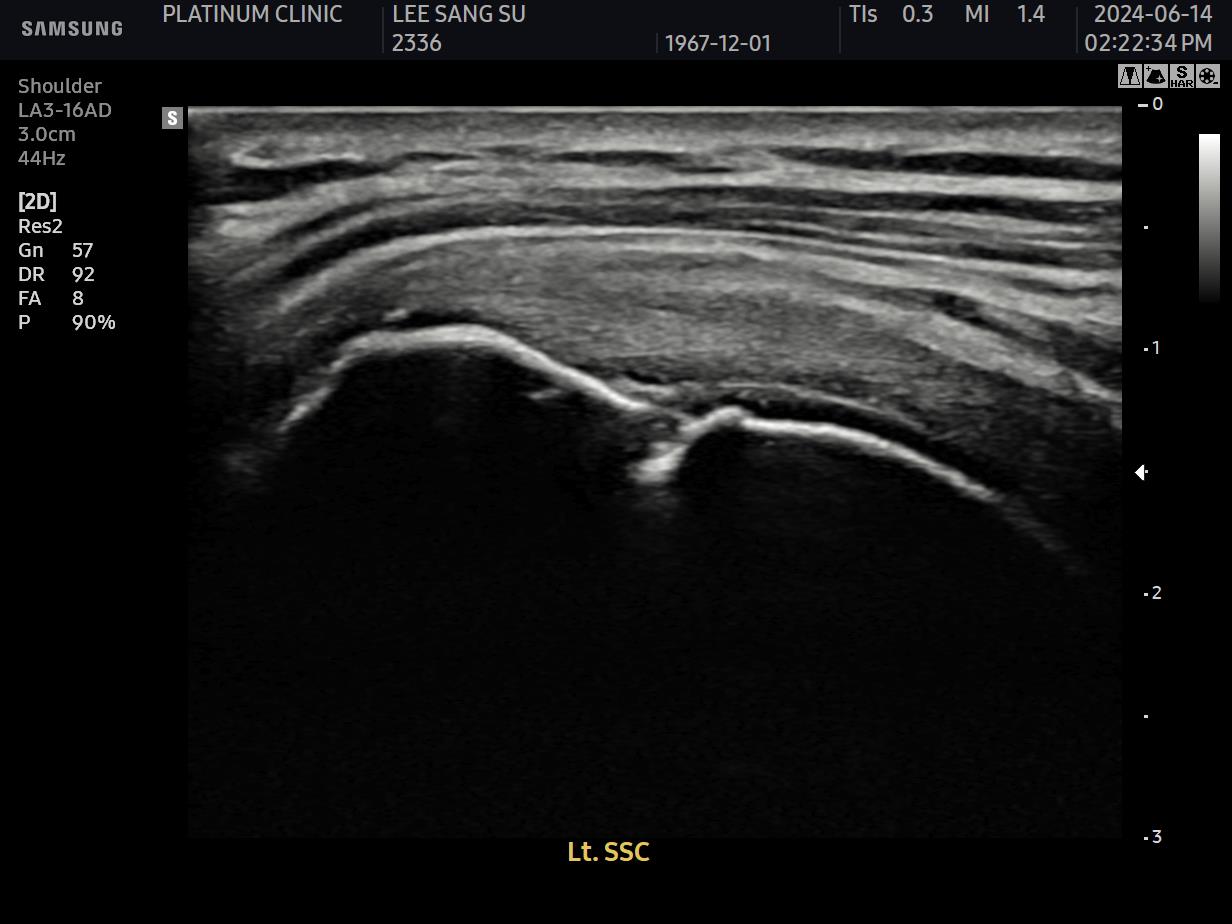

초음파 검사로 확인할 수 있습니다.

치료 전 초음파에서 검게 보이던 파열 부위가, 치료 후에는 정상 인대처럼 하얗게 보입니다. 이것이 구조적 회복의 증거입니다.

안 아파요"라는 주관적 느낌만으로 치료 완료를 판단하면 안 됩니다. 영상으로 확인된 구조적 회복이 있어야 진정한 치료입니다.

12주차: 초음파로 확인된 '재생'

마지막 주사로부터 6주 후, 팔로우업 검사를 진행했습니다.

초음파 결과:

이전에 검게 보이던 파열 부위가 하얗게 재생됨

인대 두께가 정상 범위로 회복됨

주변 염증 소견 소실

세 가지 기준이 모두 충족되었습니다.

환자분, 이번에는 진짜 치료가 끝났습니다. 초음파에서도 재생이 확인되었고요. 이제 재활 운동만 꾸준히 하시면 됩니다.